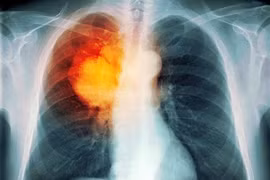

Ung thư phổi là một trong những dạng ung thư nguy hiểm nhất. Vì các dấu hiệu cảnh báo có xu hướng xuất hiện khi các tế bào ung thư đã nhân lên và lan sang các khu vực lân cận trong cơ thể.

Số bệnh nhân châu Á chiếm khoảng 60% tổng số ca ung thư phổi trên toàn thế giới, trong đó riêng Việt Nam có hơn 26.200 trường hợp được chẩn đoán mắc mới mỗi năm và gần 23.800 ca tử vong.

Theo chuyên trang về sức khỏe Hoa Kỳ webmd, nguyên nhân gây ung thư phổi phát sinh chủ yếu từ môi trường bên ngoài. Nắm được những tác nhân này sẽ giúp bạn hạn chế nguy cơ mắc bệnh.